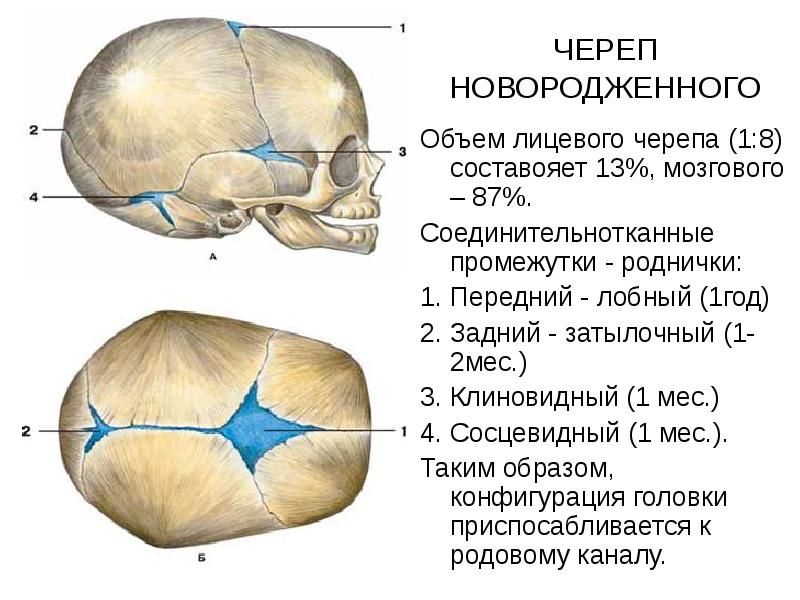

Анатомические изображения срединной сагиттальной линии черепа